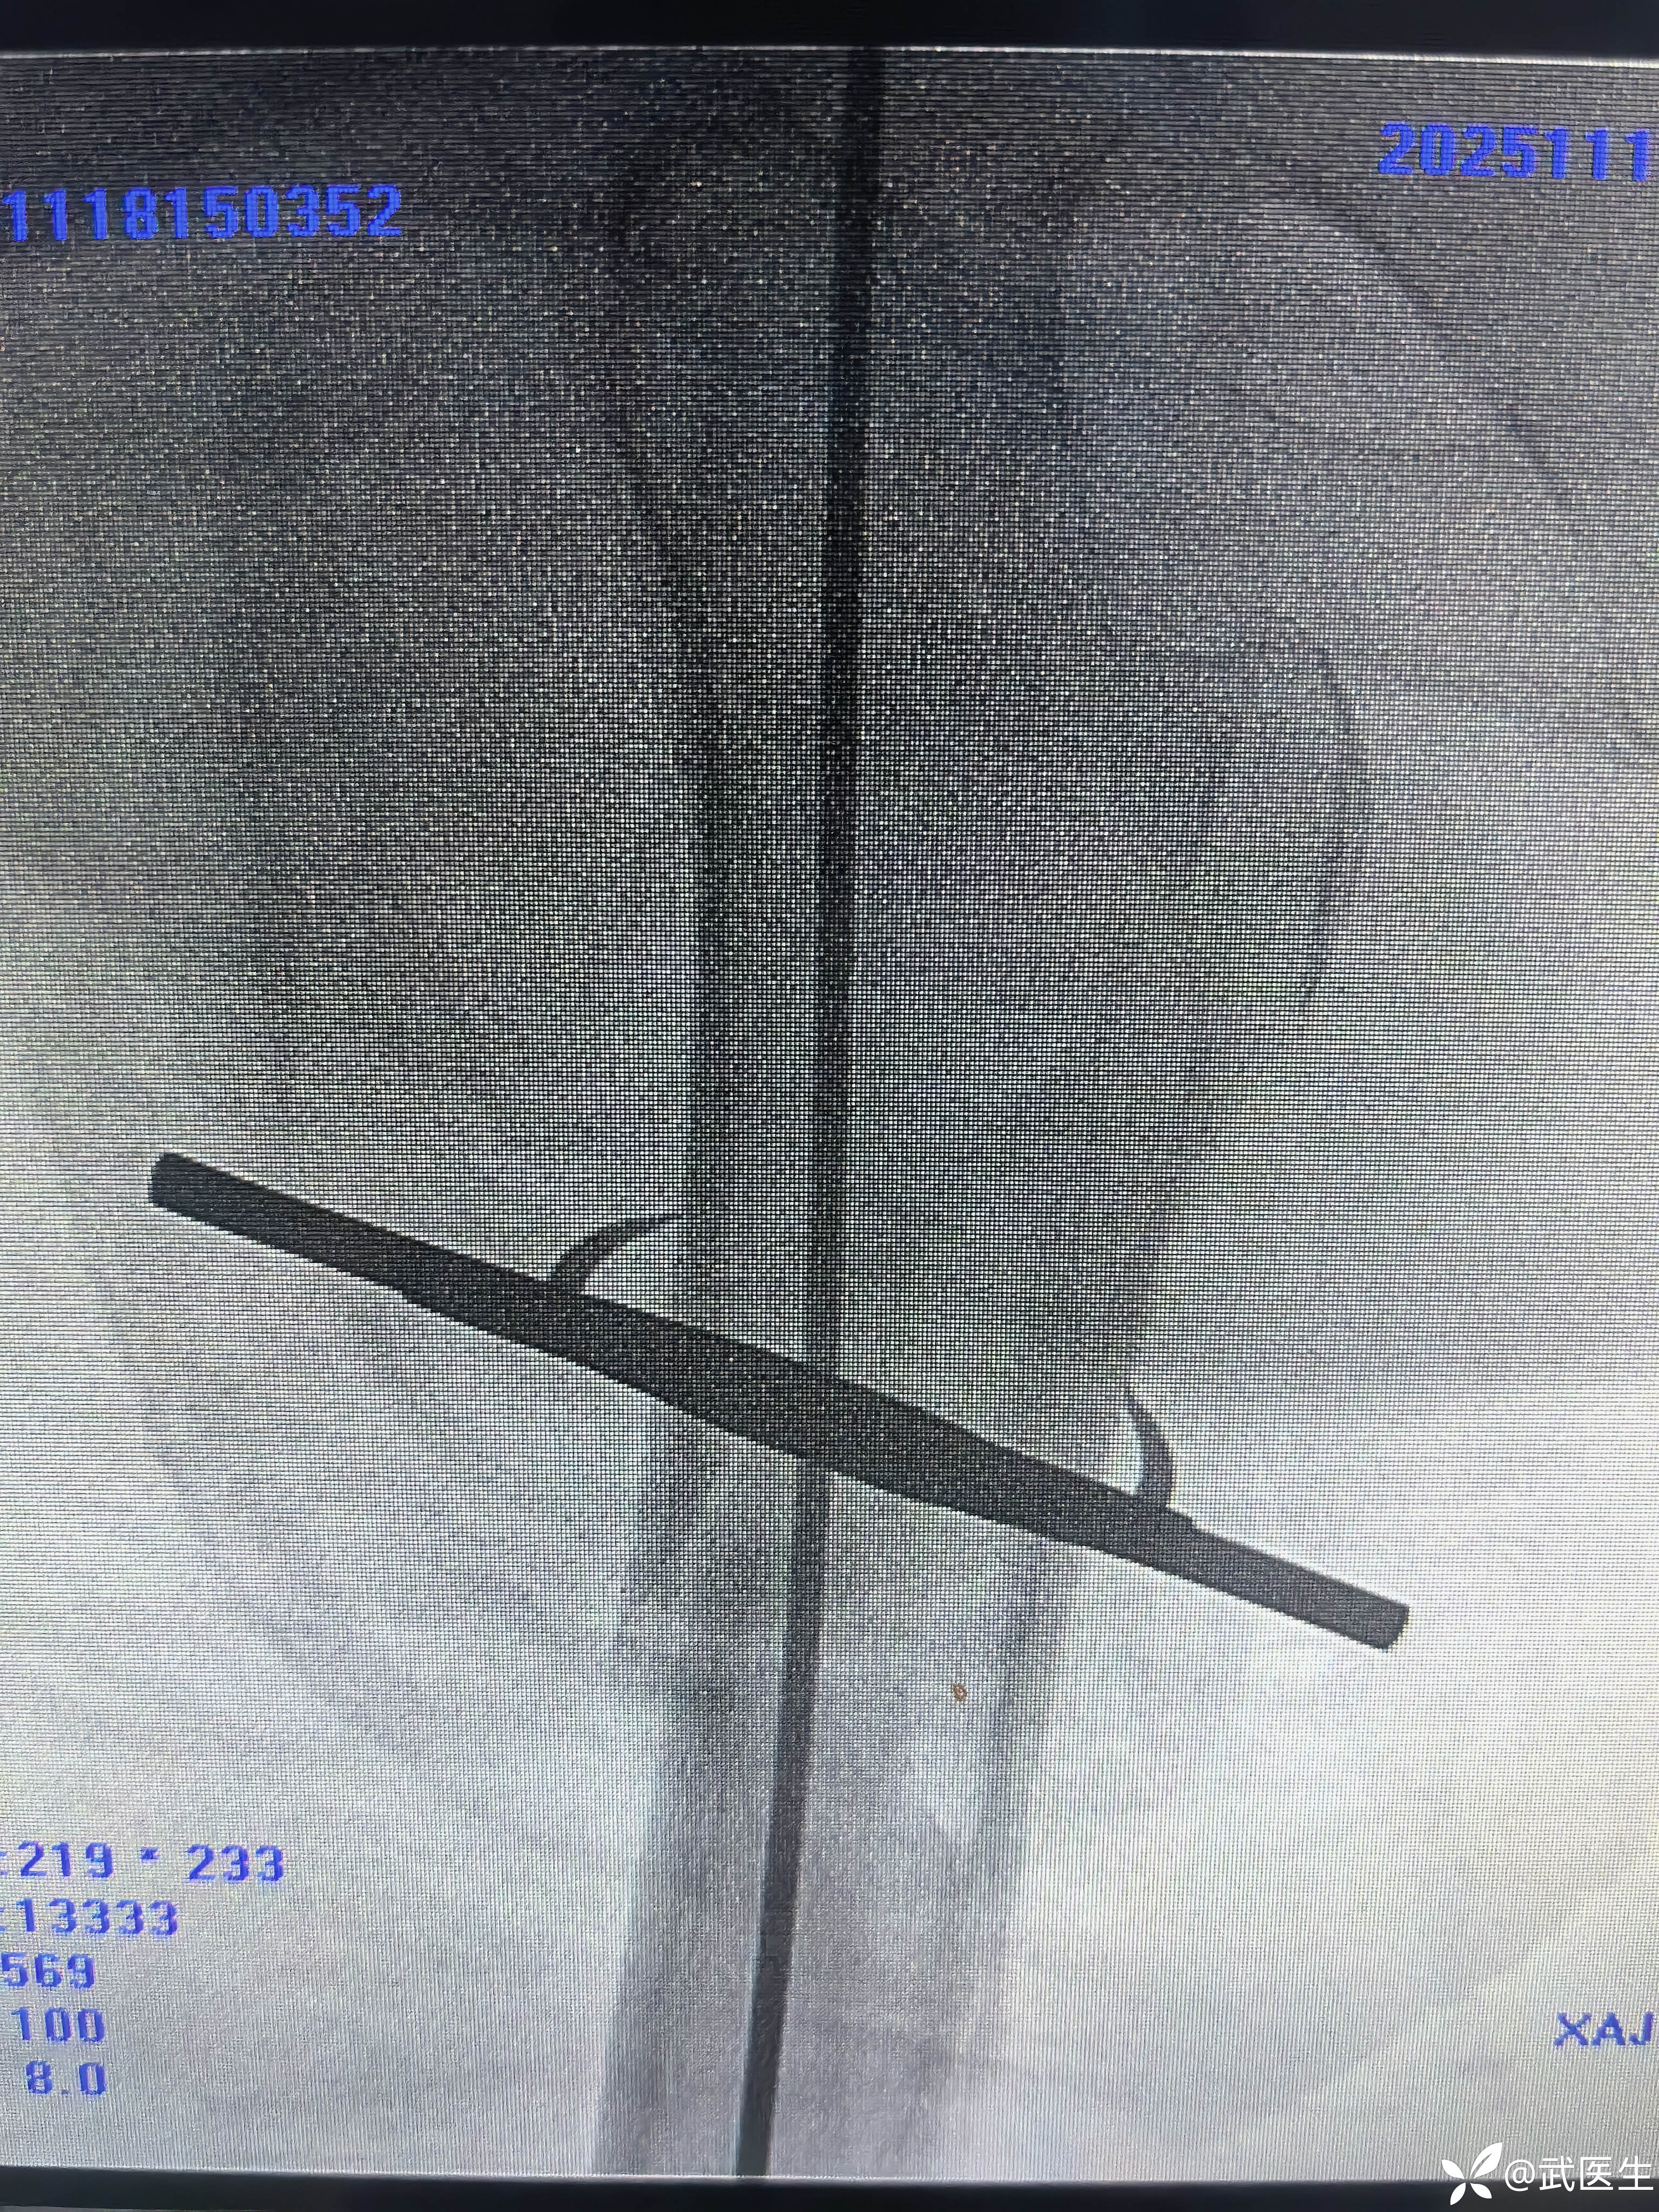

术后常规手术室拍片,如下

正位,骨折对位良好,头颈钉居中偏下,髓内钉顶天立地。

轴位,呦吼,啥情况,后方这个大尖尖……

不处理了,切口如下

如术后侧位图片,各位战友你会返工捆绑钢丝么?